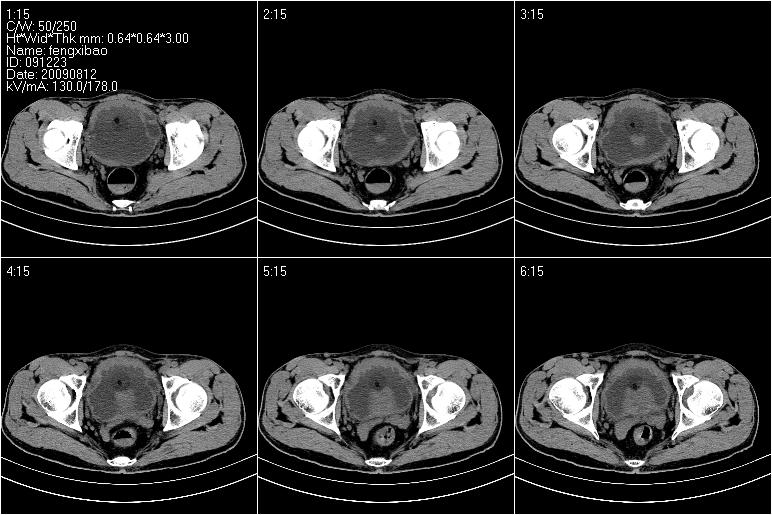

标题: CT21568:男,57岁,双肾及输尿管重度积水。彩超示前列腺占 [打印本页]

标题: CT21568:男,57岁,双肾及输尿管重度积水。彩超示前列腺占

考虑前列腺增生并慢性尿潴留致膀胱肌小梁增生

考虑膀胱癌侵犯双侧输尿管末端及前列腺,双输尿管扩张积水。

前列腺增生肥大,内密度不均,ca不排外;膀胱壁弥漫性增厚,膀胱精囊三角清,炎症?

前列腺ca;膀胱炎,膀胱、直肠受累不除外

考虑膀胱癌侵犯双侧输尿管末端及前列腺,双输尿管扩张积水.

1 前列腺增生肥大,不除外癌变可能,建议mr检查

2 膀胱壁弥漫性增厚,内侧可见增粗的小梁和腺体,考虑为腺性膀胱炎

前列腺增生,内密度不均,警惕癌变,膀胱壁弥漫性增厚,考虑慢性膀胱炎。

考虑前列腺增生症并腺性膀胱炎,双侧输尿管扩张;建议必要时行mri检查。

1、前列腺改变主要为中央区,考虑前列腺增生可能性大。

2、膀胱壁弥漫性增厚,考虑膀胱炎可能,请结合临床。

考虑前列腺增生并慢性膀胱炎。不除外前列腺癌可能。建议结合其它检查。

考虑:前列腺增生并慢性膀胱炎。不除外前列腺癌可能。建议结合其它检查。